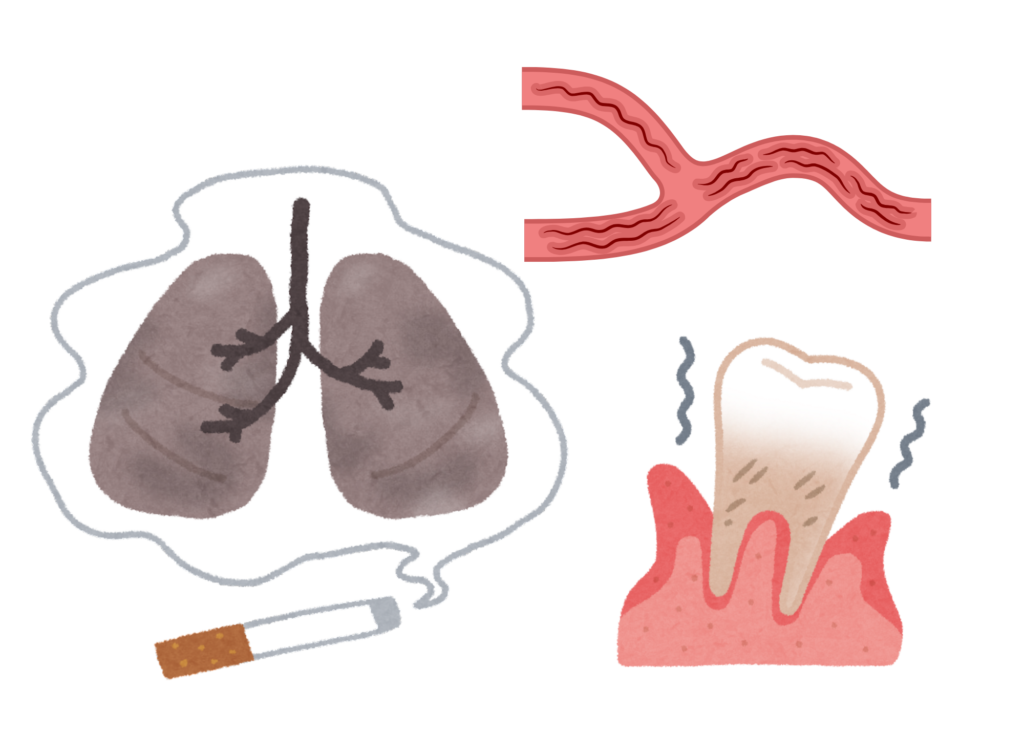

喫煙と歯周病:歯周病にかかるリスクが2〜9倍

歯周病の進行において、タバコは「最大の発症・悪化因子」と言われています。喫煙習慣がある方は、吸わない方に比べて歯周病にかかるリスクが2〜9倍、さらに歯を失うリスクも約3倍高まることがわかっています。

心臓病・脳梗塞(動脈硬化性疾患)

歯周病菌や炎症性物質が血管内に入り込むと、動脈硬化を誘導する物質が産生され、血管内にプラーク(脂肪性沈着物)ができやすくなります。これにより、狭心症や心筋梗塞、脳梗塞などのリスクが高まると考えられています。

誤嚥性肺炎

誤嚥性肺炎は、食べ物や唾液が誤って気管に入り、お口の中の細菌が肺で増殖して起こる肺炎です。特にご高齢の方では、歯周病菌などの口腔内の細菌が原因となるリスクが高いことが知られています。